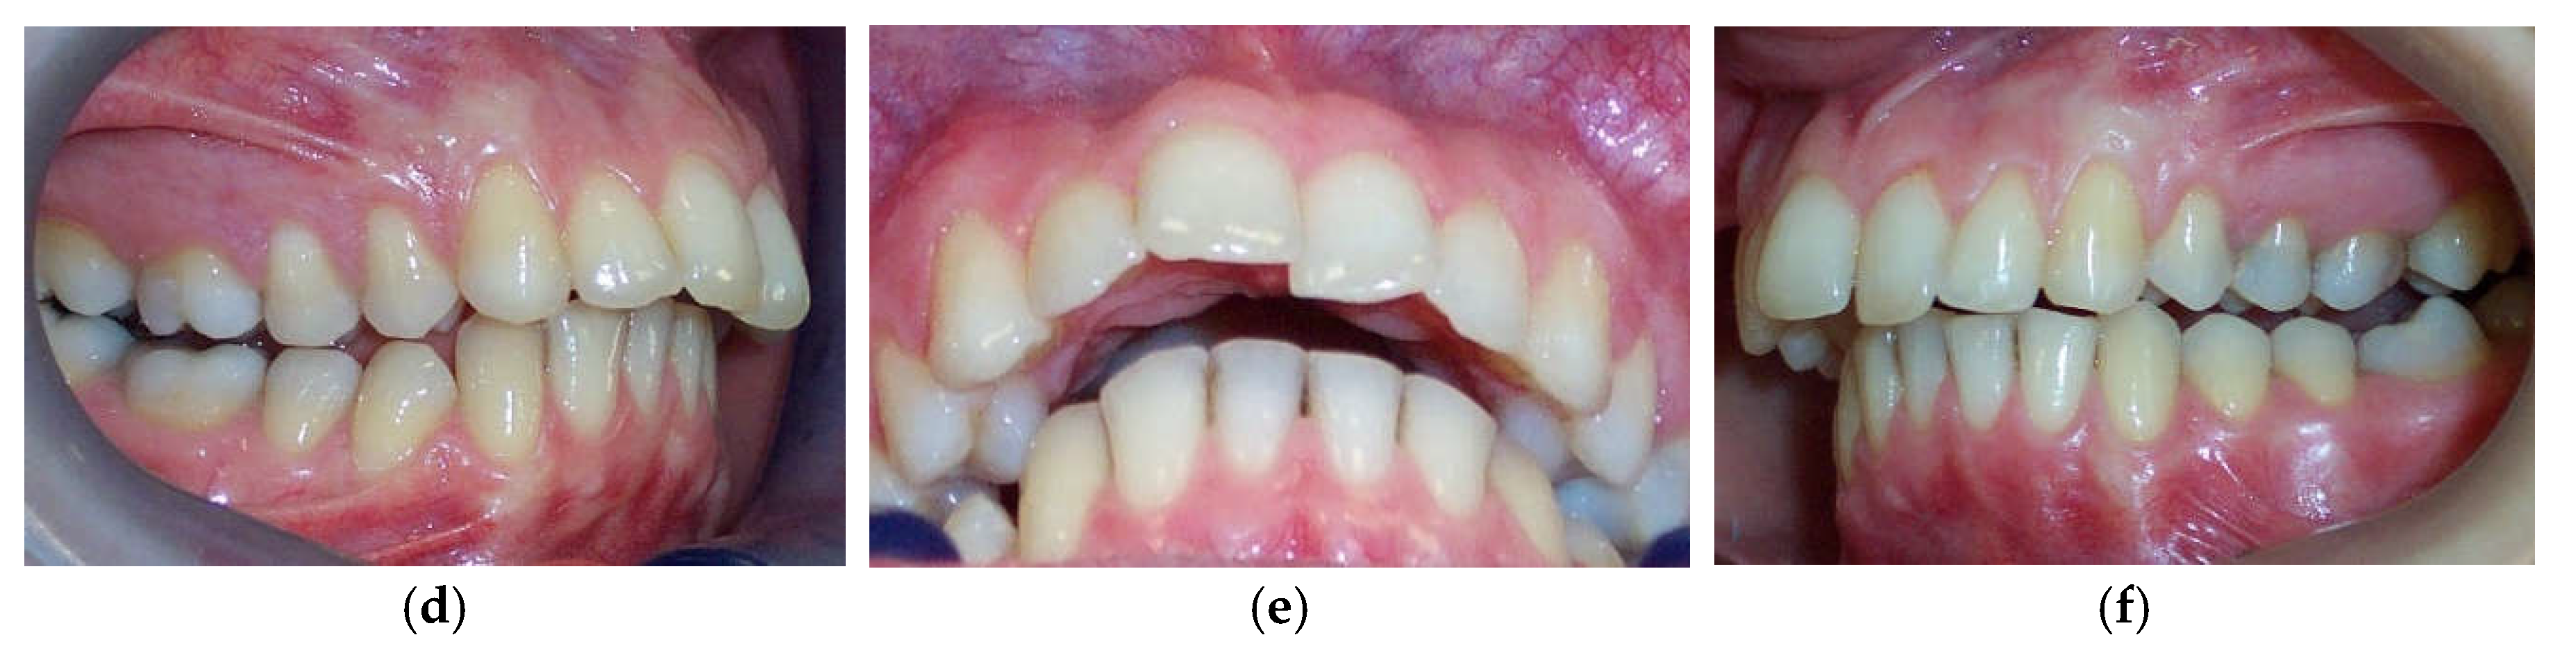

According to Spearman’s correlation, test results of the anamnestic and diagnostic criteria of RDC/TMD were strongly positively correlated (p < 0.05) with the condylar displacements in the vertical and transverse planes before the splint therapy. When compared before and after, interarch relationship changes were observed intraorally and from models mounted on a semi-adjustable articulator after the neuromuscular deprogramming (Figure 5).

The significant reduction in condylar displacement and the achievement of an orthopedically stable musculoskeletal position following the splint therapy directly correlated with the improvement in TMD symptomatology. Hence, the pain related to the area of the temporomandibular joint and masticatory muscles reported by 55% of patients before the splint therapy was completely eliminated after the splint therapy, and this result was the same for the intermittent jaw locking. Following the splint therapy, headache symptoms were reduced for more than 90% of patients, corresponding with the study findings of Kemper and Okeson [44]. After the splint therapy, jaw clicking was reduced for more than 80% of patients. Clinical findings regarding the signs of tenderness on palpation in the masticatory muscles, lateral pole, temporalis tendon, and posterior attachment inside the ear showed a statistically significant reduction in signs after the splint therapy. Crawford reported a significant increase in the signs and symptoms of TMD as the condylar displacement in vertical and horizontal planes was raised from 1 to 2 mm [12]. He et al. demonstrated that 72.9% of pre-treated orthodontic patients with signs and symptoms of TMD had a condylar displacement greater than 1 mm in the vertical and horizontal and 0.5 mm in the transverse plane, while only 11.4% of asymptomatic patients in the control group had increased condylar displacement. They then concluded that the condylar displacements identified in symptomatic patients were a significant contributory factor to the development of signs and symptoms of TMD [15]. This study found that the significant reduction in condylar displacement obtained via the splint therapy directly correlated with the improvement or elimination of signs and symptoms of TMD, concurring with the findings of similar investigations [7,12,22,23,24,29]. Moreover, our results agreed with those of authors who found a positive correlation between therapy with an occlusal splint constructed in the CR position and improvement in TMD symptomatology, albeit that in these investigations, CPI evaluation was not used [45,46,47,48,49]. Furthermore, a significant increase in condylar displacement between the CR and MI generates changes in the dental relationship that can be observed intraorally in the CR position and from dental casts mounted in the CR. Changes in dental interarch characteristics that occur following deprogramming of the neuromuscular system are presented in Figure 7 and Figure 8.

Figure 5. Interarch relationship changes in the same patient observed intraorally and from stone models mounted on an articulator. (a) Pre-splint right lateral intraoral view of occlusion in the MIP. (b) Post-splint right lateral intraoral view of occlusion in a stable musculoskeletal position. (c) Right lateral view of stone models in the MIP mounted on a CPI articulator. (d) Right lateral view of stone models mounted in the CR after neuromuscular deprogramming with a stabilization splint. The magnitude of horizontal interarch discrepancy has increased while the magnitude of vertical interarch discrepancy has decreased.